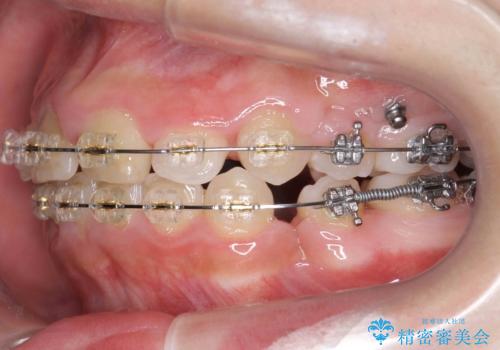

- プラスチック装置

神経の治療を先に行い、ワイヤー矯正を行いました。

上下の小臼歯を抜歯しています。